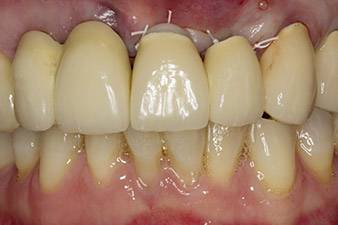

В това научно изследване, ситуацията е разрешена с имплант в позиция от първата процедура и допълнителен имплант на мястото на екстрахиран зъб 23 по-късно в хода на лечението. Вторият имплант е поставен след успешна остеоинтеграция на имплант 22. Ревизираният мост е поставен отново, докато имплант 23 заздравее на място и оформянето на перманентното възстановяване е завършено. Предимствата на този надграждащ подход включват възможността имплантите да понесат по-гъвкаво натоварването и пълноценно да се развият твърдите и меките тъкани (5).